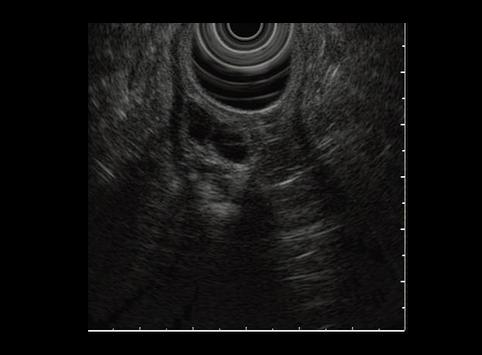

A case of heterotopic pancreas in the stomach.

[ Image ID:6956 ]

Criteria of Hist.Classification

Tumor-like lesions/ectopic mucosa

Location

Stomach/Antrum

Technique, Method

Ultrasonography

Size

30 - 34